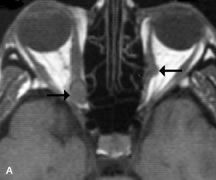

Muscle Disorders

Extraocular muscle enlargement in patients with thyroid-associated orbitopathy is demonstrated equally well with CT and MRI studies. However, the superior tissue contrast on MR images reveals better details of the relationships of the optic nerve to the thickened muscles at the orbital apex (Fig. 16).50 In addition, MRI may be able to differentiate between muscles that are enlarged as a result of edema and active inflammation and those enlarged because of fibrosis by their T2 relaxation times.21 Quantitative MRI was not found to be accurate in predicting the success of low-dose orbital irradiation.51 However, a muscular index relating the diameters of the rectus muscles to the bony orbital dimensions was useful in predicting optic nerve compression.52

Fig. 16. A-C, T1-weighted MR scans obtained with a high-resolution surface coil demonstrate fusiform enlargement of the extraocular muscles. The medial, lateral, and inferior rectus muscles are especially involved. Note the relative sparing of the tendinous insertions, a finding characteristic of this disease process, as well as fatty infiltration of the lateral and inferior rectus muscles. There is marked proptosis, best visualized on the sagittal image (A), and mild crowding of the optic nerve at the orbital apex.